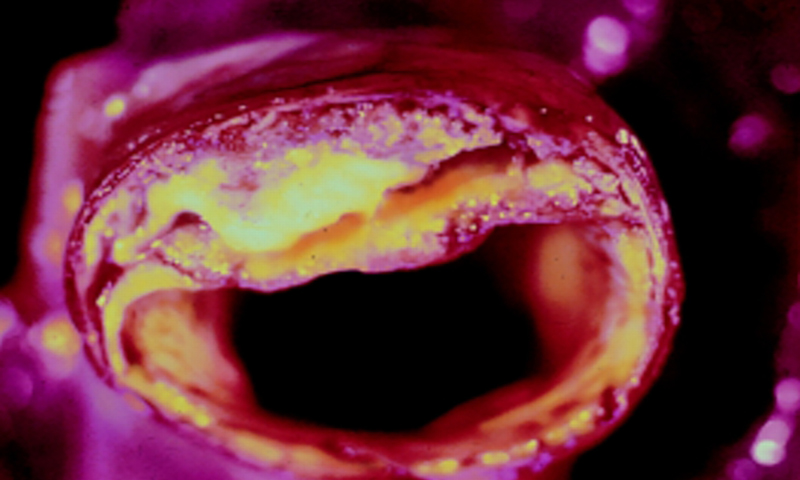

Artères bouchées

Si vos artères sont bouchées, sachez qu’il existe trois ingrédients efficaces qui peuvent améliorer, voire déboucher, les artères bouchées et éliminer la graisse du sang.

Les artères transportent les nutriments et l’oxygène vers le cœur et les autres organes du corps. Pour préserver votre santé, les artères doivent rester propres en permanence. C’est pour cette raison que l’alimentation est extrêmement importante pour vous et vos artères. Les produits transformés, les aliments gras, les toxines et les produits chimiques peuvent avoir des effets graves sur la santé cardiovasculaire et avec le temps ils peuvent entraîner des problèmes cardiaques graves.